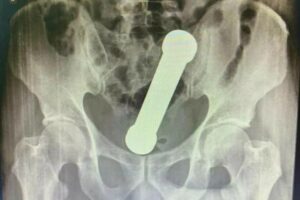

PESO DE ACADEMIA Médicos encontram peso de academia dentro de paciente em Manaus Médicos encontraram um peso de dois quilos, e cerca de 20 centímetros de comprimento dentro… há 4 anos